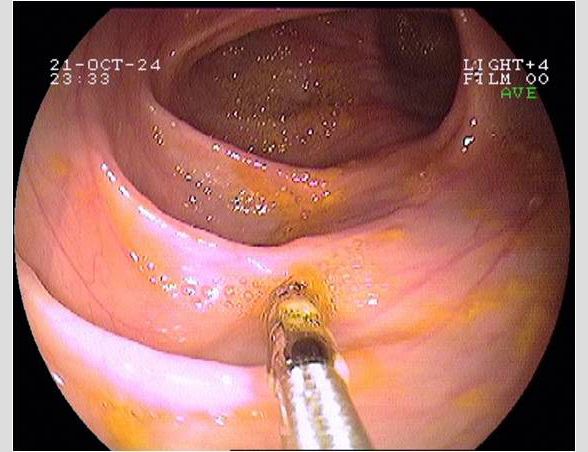

Imágenes tomadas durante la endoscopia digestiva alta y la colonoscopia. Se aprecia una mucosa de aspecto y vascularización normal, sin lesiones visibles. Se progresa con el colonoscopio hasta el íleon. Todo resulta macroscópicamente normal. Se toman biopsias de todos los segmentos explorados.

La endoscopia es el método de elección para el diagnóstico y seguimiento de la EII. Permite una visión macroscópica de la mucosa intestinal y la toma de múltiples biopsias para el estudio histológico.

Realizamos una endoscopia digestiva alta y una colonoscopia a la paciente con toma de biopsias, obteniendo el informe de Anatomía patológica.